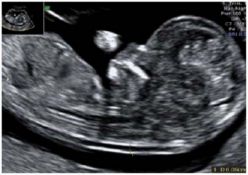

Je me pose la question car j'ai fait une echo vendredi (13sa), la clarté nucale était de 1cm Une amie avait une mesure de 17cm à 12sa ;Plus la clarté nucale augmente, plus le facteur de risque de trisomie ou autre anomalie chromosomique augmente Le bébé sur l'image de gauche a une clarté nucale de 6mm et a donc un risque élevé d'être atteint du syndrome de Down ou d'une autre anomalie chromosomique (source Witters and Frynns 07) et de problèmes cardiaques (source Wald et al 08) Une photo en 3D, à quoi ça ressemble ?

Fœtus âgé de 11 SA et 2 jours (longueur crâniocaudale = 45 mm) et ayant une clarté nucale à 4,8 mm Caryotype fœtal normalEn quoi estce utile pour l'échographiste ?Échographie de clarté nucale fœtale au 1er trimestre Service disponible Procrea Montréal et Gatineau Échographie fœtale détaillée au 2e et au 3e trimestre Service disponible Procrea Montréal et Gatineau Datation Service disponible Procrea Montréal et Gatineau Échographie 3D/4D (Service disponible chez Procrea Gatineau) L'attente d'un bébé est l'une des expériences

Mes amies elles leur gygy les envois chez des spécialiste en echo pour faire la morpho moi mon gygy a une echo qui date de la guerre hihih et en plus j'ai aps l'impression qu'il vois trop trop car il peu jamais me dire le sexe et tout celle qui vont chez lui il leur a dit qu 7ème mois!!!!Pour bébé 1, clarté nucale à 4 panique, peurs, questions, impuissance tout se mélanger dans nos têtes, au papa et moi Nous avions, bien réfléchi, sur le court comme le long terme, et avons décider de ne faire aucuns examens complémentaires, si bébé était trisomique, nous le gardions!Fœtus âgé de 13 SA (longueur crâniocaudale = 66,8 mm) et ayant une clarté nucale à 3 mm Caryotype montrant qu'il s'agit d'un fœtus trisomique 21 Exemple (2) Age maternel = 37 ans ;

Lors de l'échographie en 3D, l'image est colorisée artificiellement en rose pour la rendre plus réaliste"Elle n'a pas tout à fait la même forme que le bébé" prévient Danièle Combourieu, car "la sonde que l'on tourne sur le ventre de la maman est beaucoup plus large pour contenir le capteur"En somme, il prend plusieurs plans et laLa mesure de la clarté nucale (mesure de l'épaisseur de la nuque, comme montré à coté avec la flèche rouge) se fait à l'échographie du 1 er trimestre, environ entre 11 et 13 semaines et 6 jours d' aménorrhée (c'est très précis), entre 45mm de longueur d'embryon mesuré entre la tête et les fesses et 84mm sinon en dessous et audessus les échographistes n'ont pas lesDonc c'est pour ca!!!